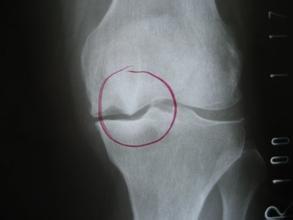

区分骨质增生和骨质增生症

骨质增生一般不会引起症状,所以不能说疼痛就拍片,然后发现有骨质增生就一口咬定它就是疼痛的原因、把它当成病,那可是会导致误诊误治的。

只有增生的骨刺刺激到了局部组织或周围神经而产生症状的时候才叫骨质增生病。

真正的骨质增生